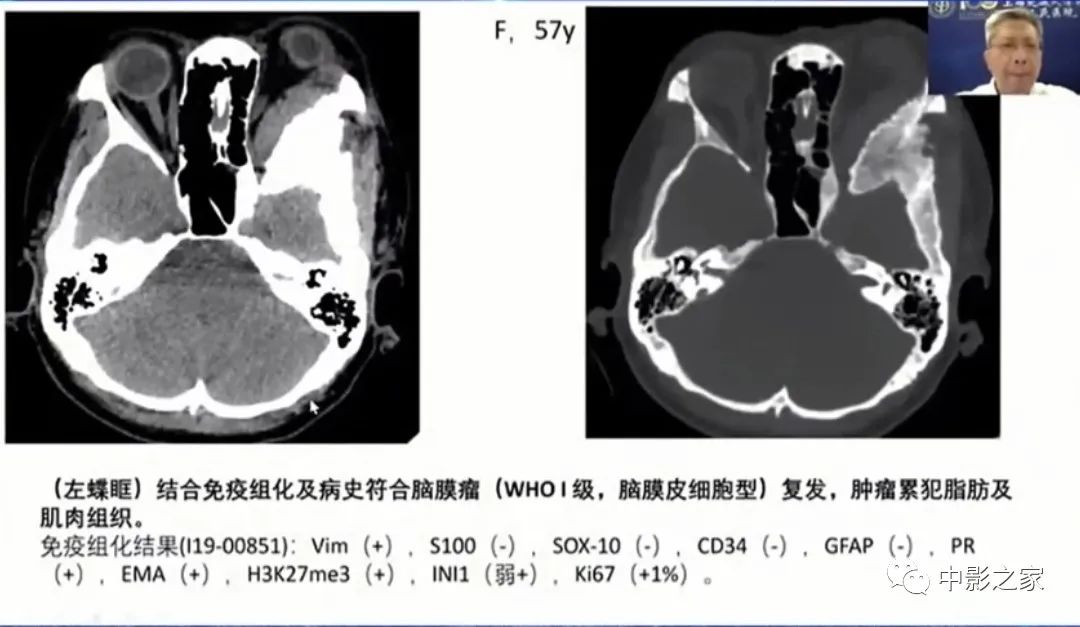

来源:2022年REACH神经影像系列巡讲一广东站